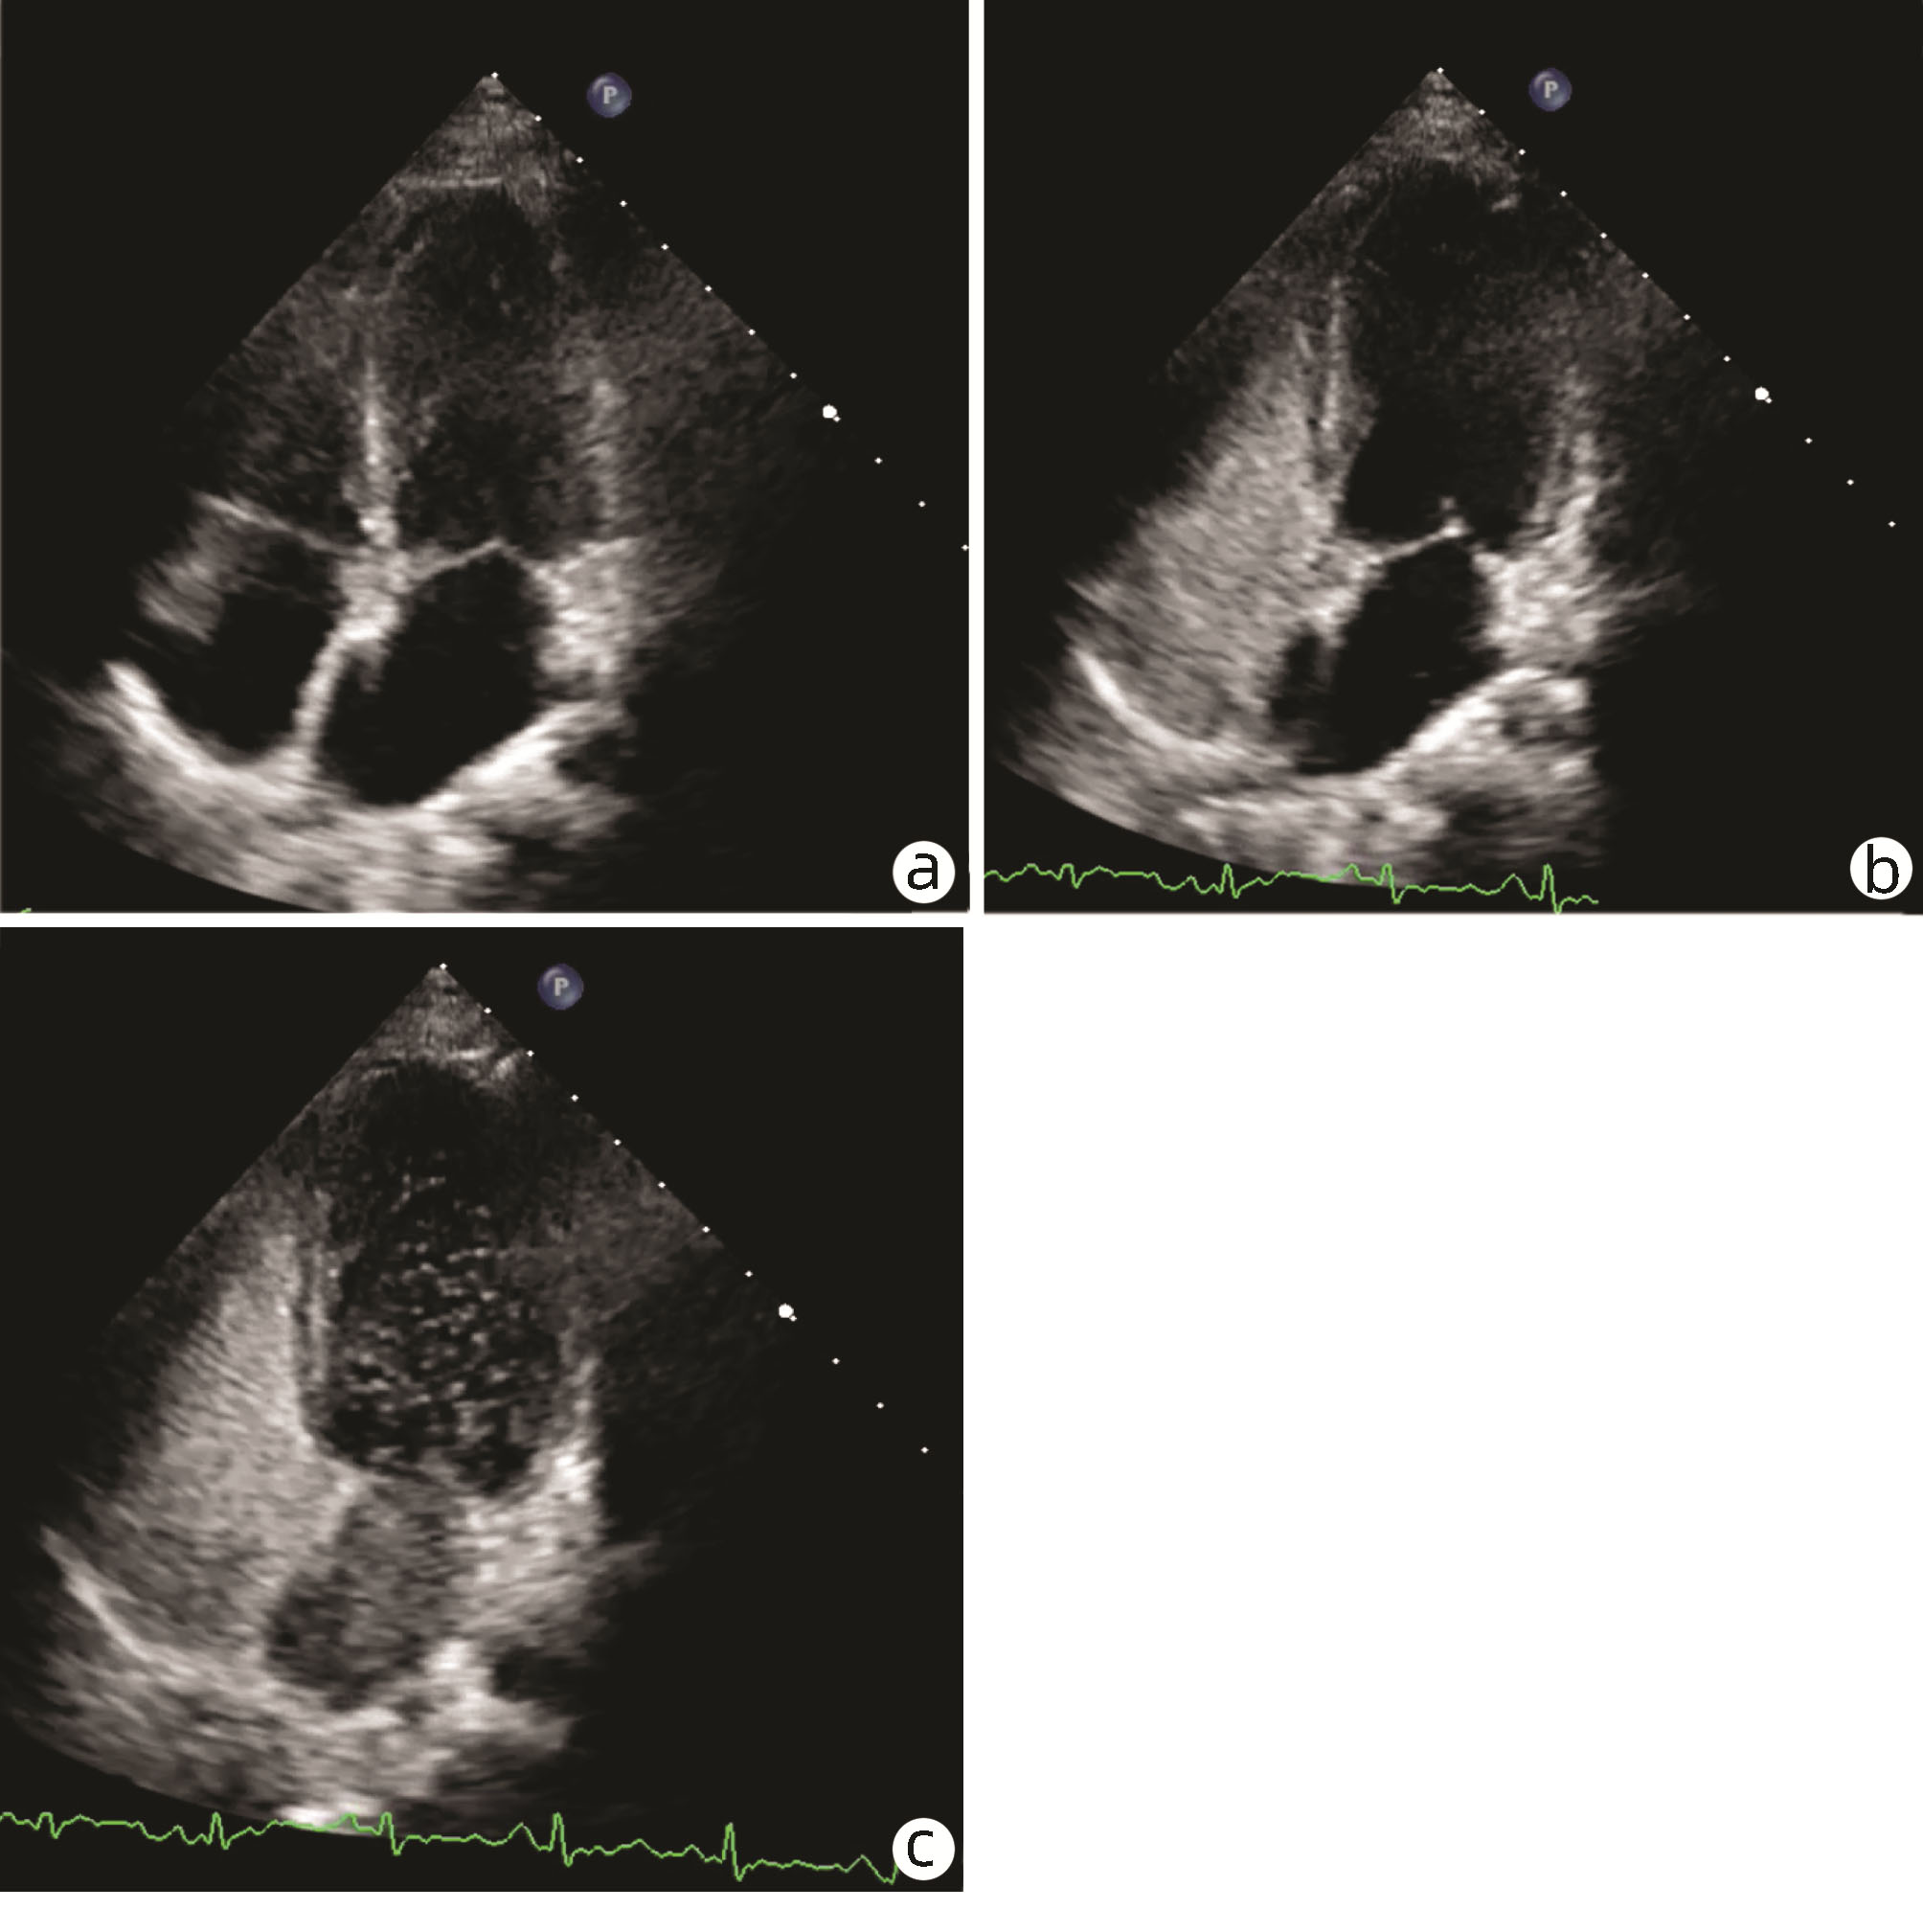

Hepatopulmonary syndrome after craniopharyngioma operation in children: A case report

Tingting DU, Hui YAO, Yakun LI, Xiaoli HUANG, Jie LUO

2022, 38(7): 1620-1625. DOI: 10.3969/j.issn.1001-5256.2022.07.030

Abstract(1037) HTML (325) PDF (2776KB)(79)

Abstract: